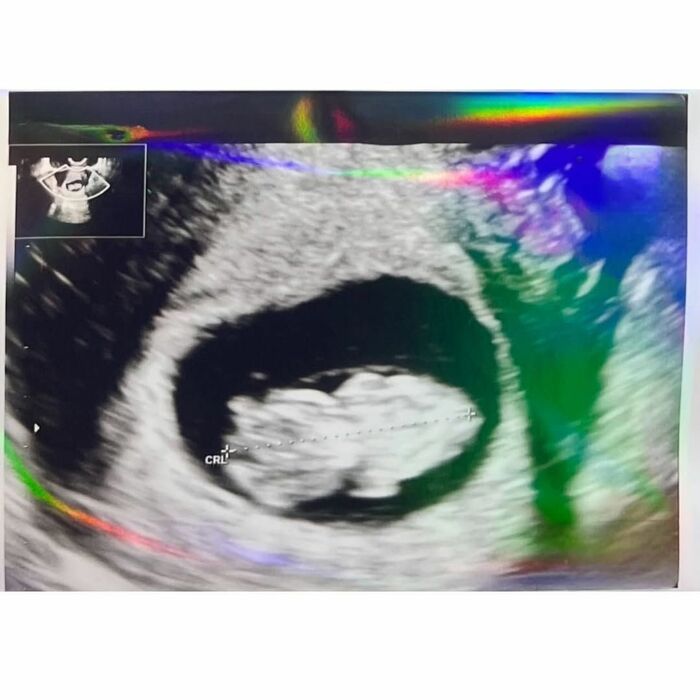

さらに、エコー写真も公開しており、まだ顔は分かりませんが、赤ちゃんの姿が捉えられていました。